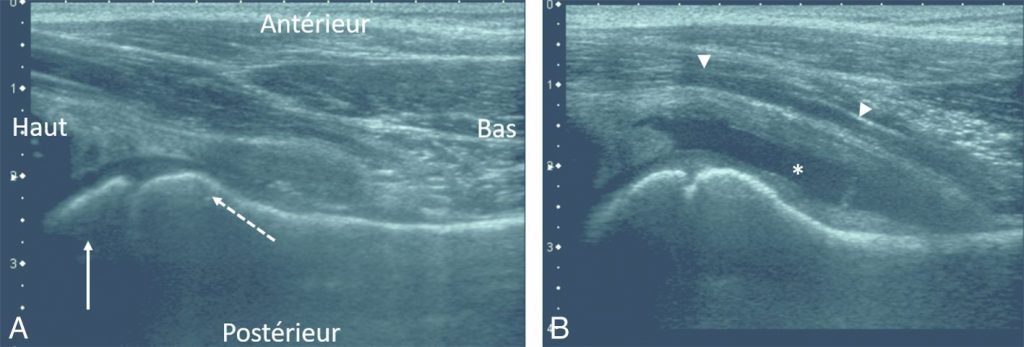

L’échographie met en évidence un épanchement intra-articulaire de façon inconstante (figure 114.1).

Fig. 114.1 Boiterie aiguë gauche chez une enfant de 5 ans sans fièvre.

La radiographie du bassin de face et profil était normale (non montrée). L’échographie de hanche réalisée dans l’axe du col fémoral montre une hanche droite normale (A) avec visibilité de l’épiphyse fémorale proximale (flèche blanche) et la métaphyse fémorale supérieure (flèche en pointillé) ainsi que le muscle psoas. À gauche (B), il existe un épanchement liquidien trans-sonore (∗) refoulant en avant le psoas (têtes de flèches). Ces aspects, en l’absence de fièvre et d’altération de l’état général, sont en faveur d’une synovite aiguë transitoire (rhume de hanche), qui doit être un diagnostic d’élimination.

Source : CERF, CNEBMN, 2022.